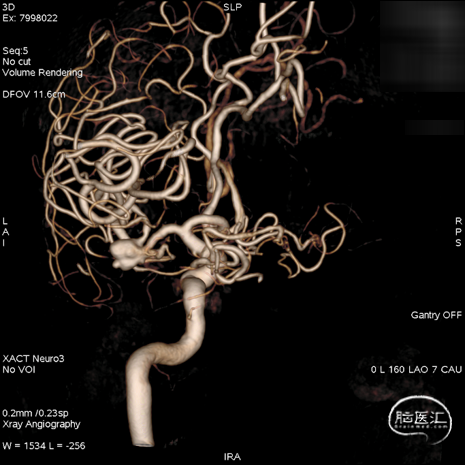

术后影像

复查标准正侧位造影, ICA、MCA、ACA主干及远端分支良好,动脉瘤栓塞满意。

术后工作位+侧位造影

术后正侧位透视

术后三维重建,支架贴壁良好,动脉瘤完全栓塞。